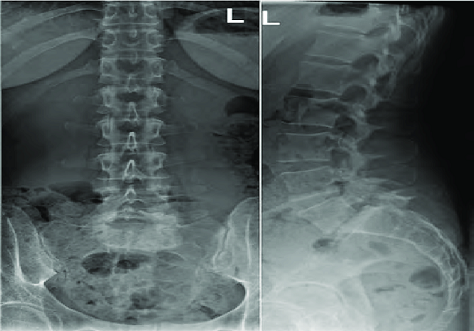

Radiographie du rachis

Egalement connue sous le nom de radiographie de la colonne vertébrale, est une technique d’imagerie médicale utilisée pour visualiser les vertèbres et les structures associées de la colonne vertébrale.